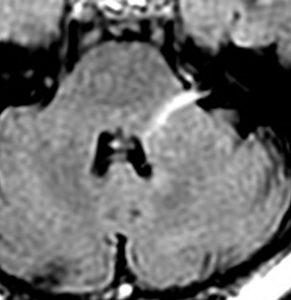

38歳の時に典型的な左三叉神経痛で発症しました。左はMRIT2,右はフレア画像です。小脳と脳幹部の間に巨大な血管がみえます。これは生まれつきの静脈の奇形 (venous anomaly)です。この血管は脳幹部と小脳のかなりの部分の血流を還流しています。出血などはみられませんが,脳幹左側の三叉神経核と神経路に血流障害があるものと推定されます。このタイプは手術で治すことができません。カルバマゼピンは有効でしたがアレルギーのために使えなくなり,ガバペンチン 1800mg/日で痛みはなんとか我慢できています。24年の間に試した他の薬は何も効きませんでした。